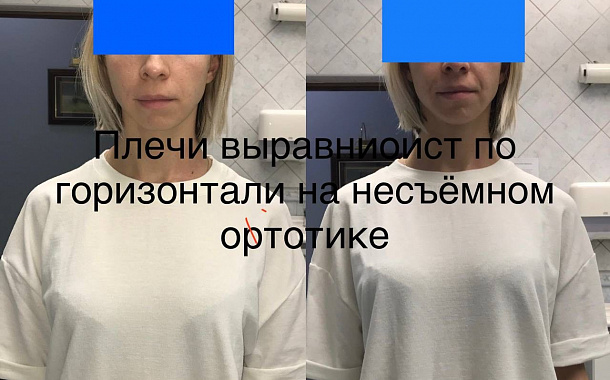

- Коррекция прикуса — если причиной хруста является неправильный прикус, мы предлагаем вам индивидуальный подход для его исправления с использованием брекетов, кап или других ортодонтических устройств.

- Ношение шины — для пациентов с диагнозом «синдром дисфункции ВНЧС» могут быть рекомендованы специальные капы или шины для фиксации челюсти в правильном положении на ночь.

Полный прайс-листКейсы: до и после